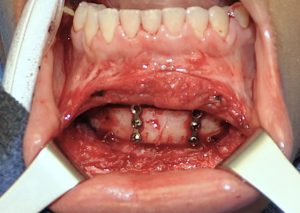

5) For vertical chin reduction I plan on removing both a wedge of bone intraorally as well as a wedge of soft tissue from underneath the chin.

6) Zygomatic or lateral cheek implants are placed through intraoral incisions. But they can also be placed through an external skin incision on the backside of the sideburn over the posterior zygomatic arch.